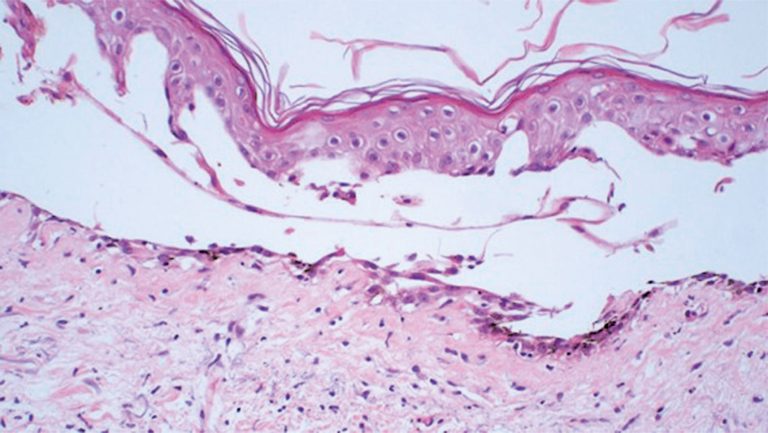

ABSTRACT Azacitidine is a hypomethylating agent recommended for the treatment of patients with high-risk myelodysplastic syndromes. Here, we report the case of a patient with myelodysplastic syndrome who was not eligible for allogeneic stem cell transplantation (allo-SCT) and presented with a rare and previously unreported cutaneous side effect after the use of subcutaneous azacitidine. We propose that changing the route of azacitidine administration from subcutaneous to intravenous could potentially decrease the occurrence of bullous pemphigoid-like localized toxic reactions in some […]